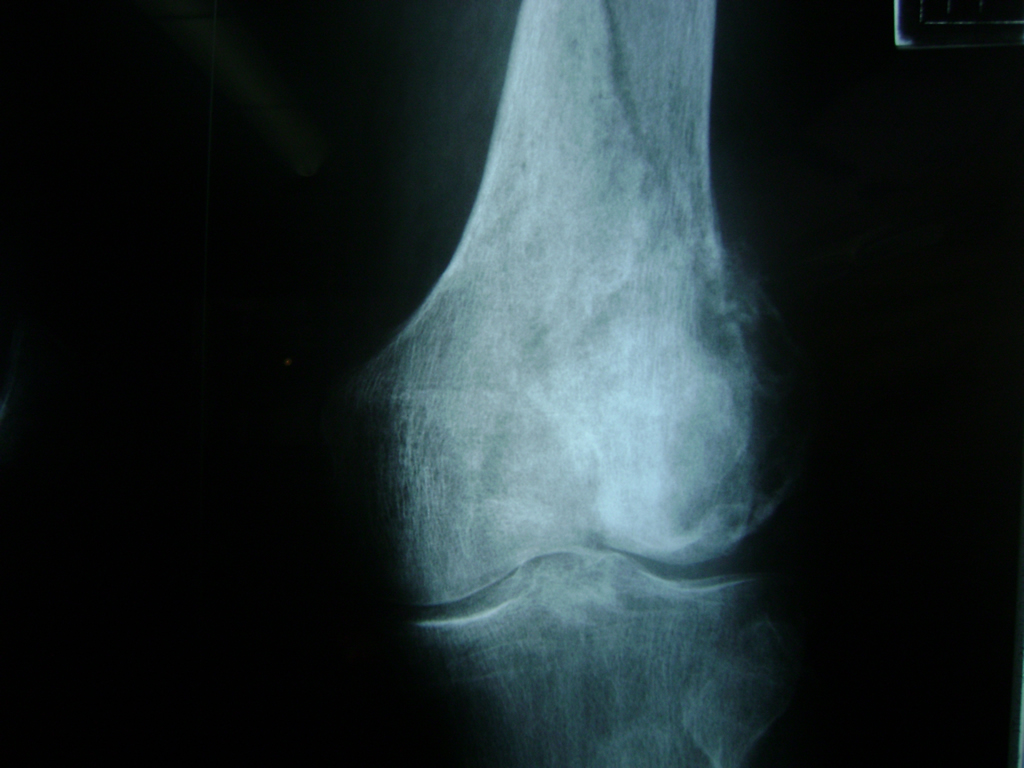

Cirugías de Húmero - Rodilla

La artroscopia de rodilla es un cirugía en el cual la estructura interna de la articulación es examinada ya sea para realizar un diagnostico o para realizar un tratamiento, este procedimiento se realiza utilizando un instrumento parecido a un pequeño tubo llamado artroscopio.